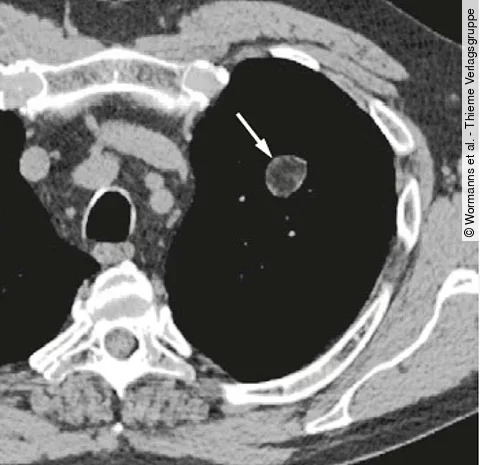

Radio-Quiz: Lungenfund bei Lehrer mit gesundem Lebenswandel

Der 50-jährige Patient kommt infolge einer Bronchusobstruktion zu Ihnen. Er pflegt einen sehr gesunden Lebenswandel, macht regelmäßig Sport, raucht nicht und trinkt selten Alkohol.